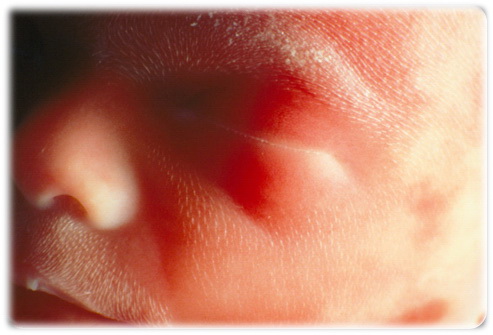

يمكننا رؤية نوع من الشعر وطبقه زيتيه مخصصه لحماية تطور الجلد. تمت الى الآن عملية تطور الحواجب ، الرموش والأظافر. يتمكن الجنين من السمع الآن

الإسبوع الرابع والعشرون .. يبدأ نخاع العظام بإنتاج كريات الدم الحمراء. إلى الآن تم تشكيل بصمات الأصابع وتم تكون مناطق الذوق على اللسان. شعر حقيقي يبدأ بالنمو على رأس الطفل. تم تخلق الرئتين ولكنهما لن تعملا قبل خروج الطفل من بطن أمه. ينام وينهض الطفل بشكل منتظم الآن. تم تشكيل البويضات عند المولوده الأنثى، وهذه البويضات ستكون جاهزه للإخصاب عند بلوغ الفتاه لمدار الفتره المتوقعه. طول الطفل يصل إلى 30 سنتيمتر ووزنه إلى 0.68 كيلوغرام